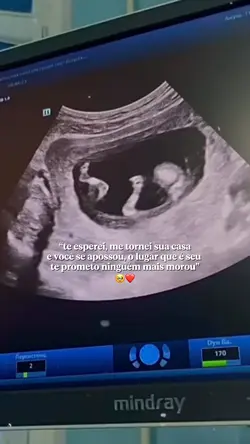

bebê no forninho 💘

Bebê no forninho

meu bebê.💘